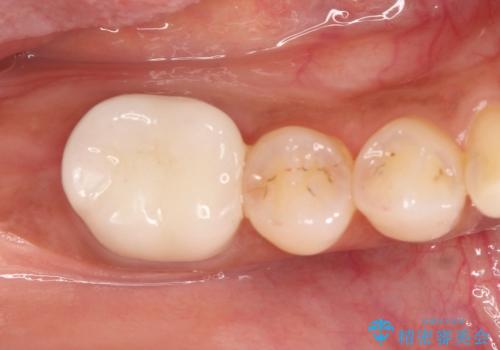

矯正治療を行なったのち、オールセラミッククラウンにて修復しております。

矯正治療はインビザラインで行なっております。